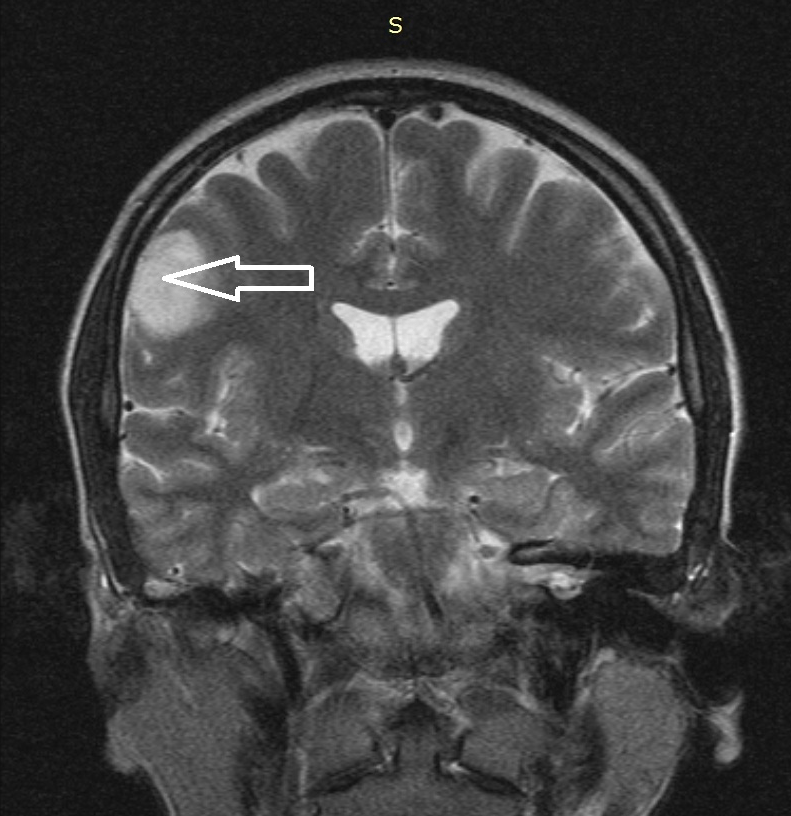

Медицинские аспекты и диагностика субдуральной гигромы мозга